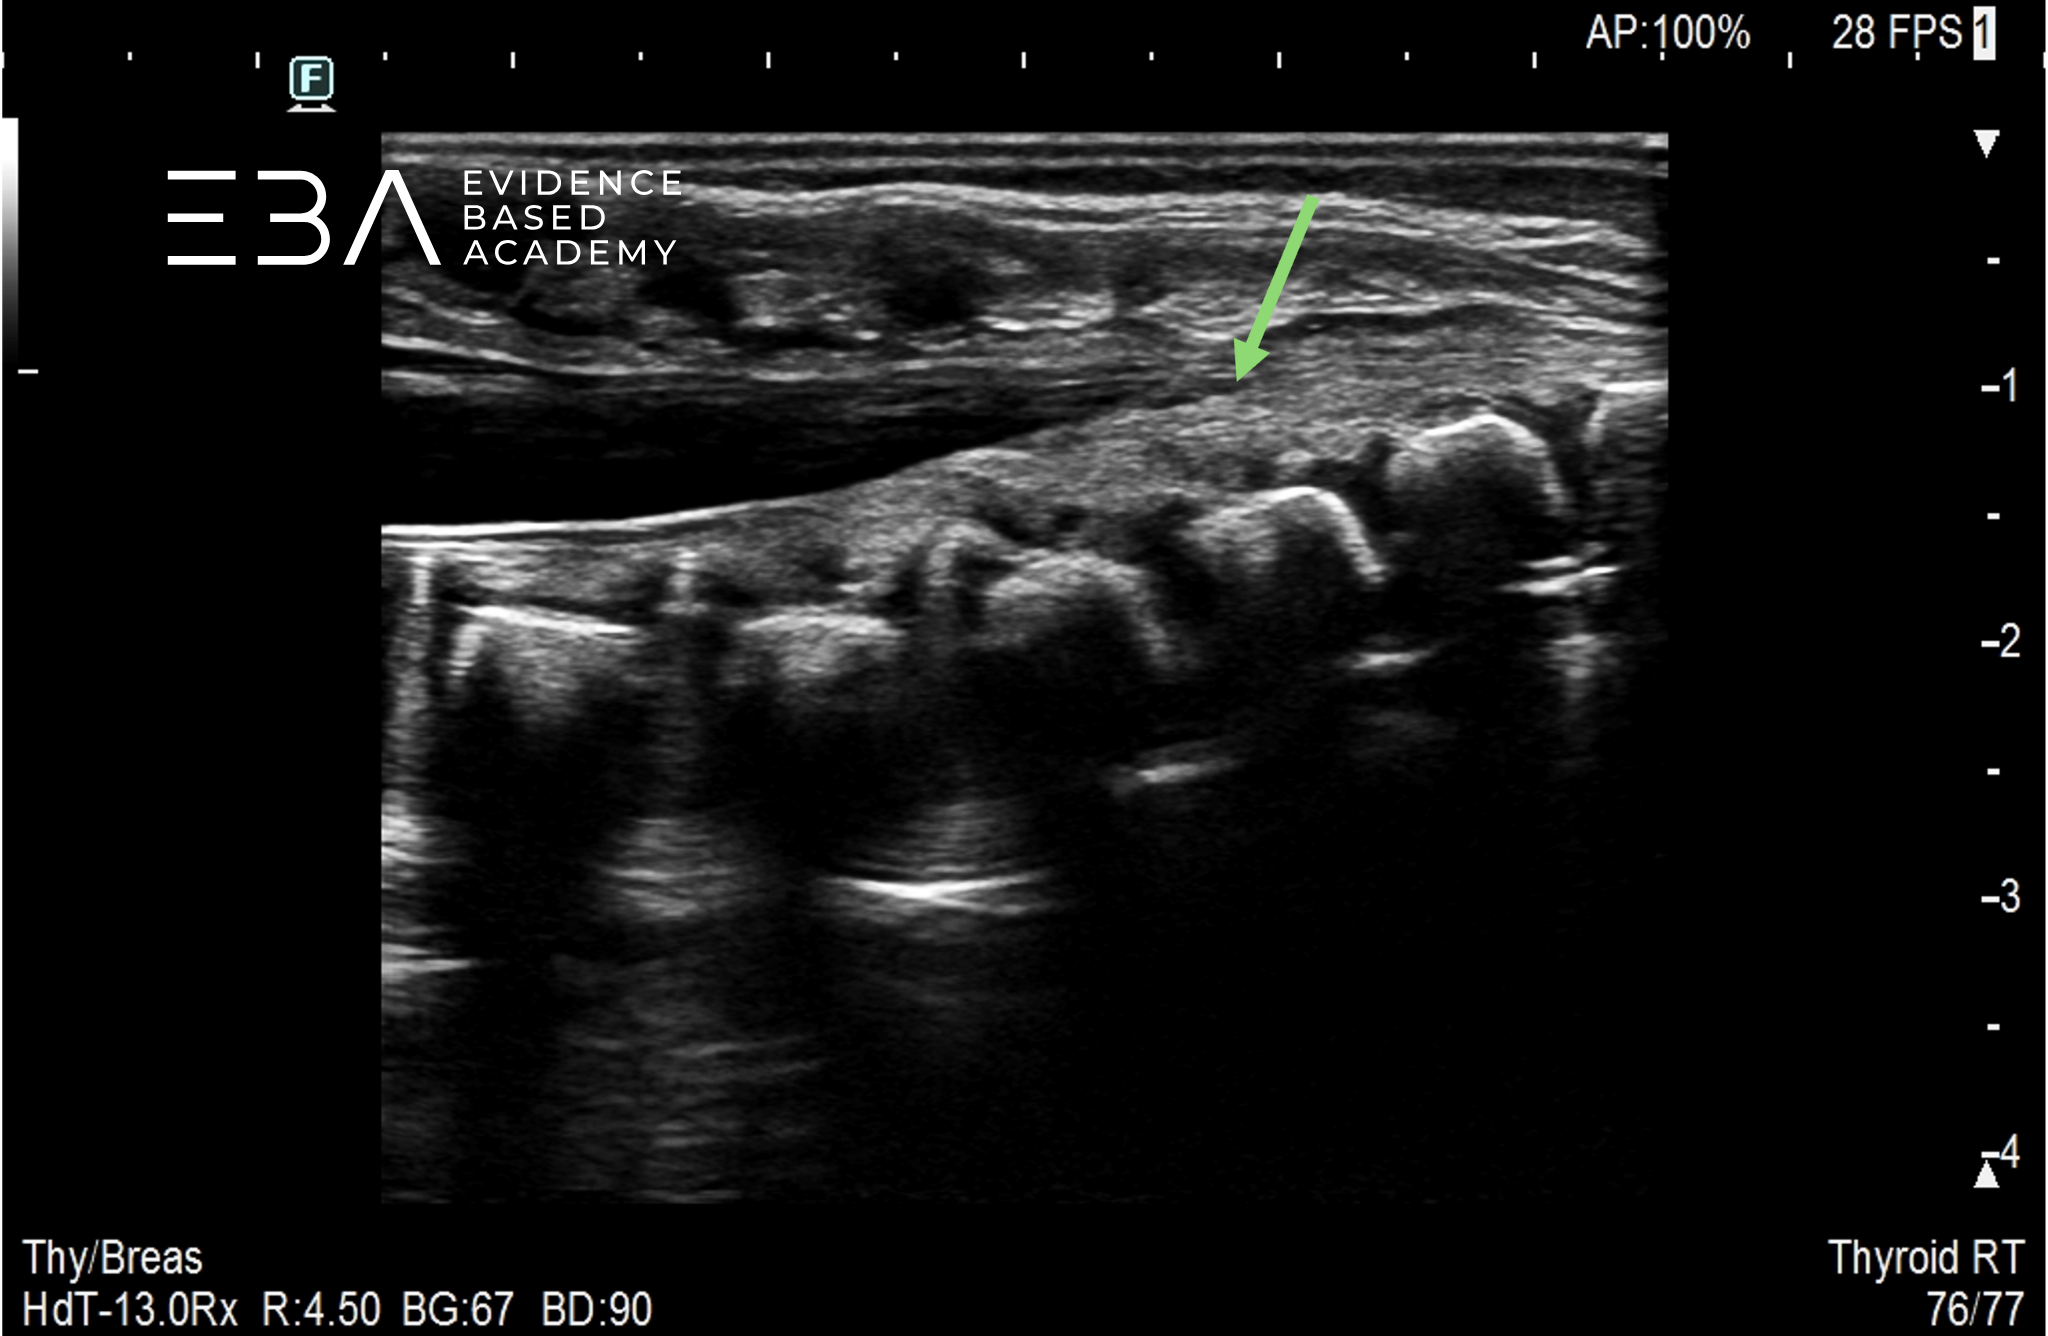

fot. 5

Kanał kręgowy, przekrój podłużny odcinka krzyżowego. Niebieską strzałką zaznaczono stożek rdzenia kręgowego, pomarańczową strzałką włókna ogona końskiego.